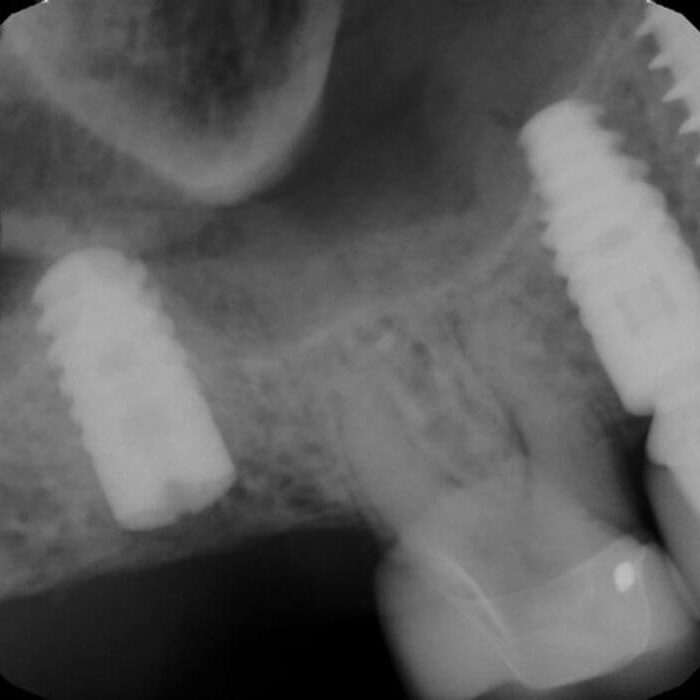

ULTRASONICS: Complications of Abutment Screw Retrieval Secondary to Prior Ultrasonic Attempts

There has been much written on the use of ultrasonics in retrieving fractured screw fragments, which I didn’t think a lot about until May of 2023, as it has not been a part of my fractured screw retrieval algorithm.